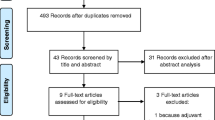

A flow chart depicted our glioma surgical activity during the study period (Fig. 1). The tumor location was reported for each patient in the following categories: frontal, fronto-callosal, fronto-temporo-insular, temporal, parietal, and occipital specifying whether it was the left or right hemisphere. The following brain areas were considered to be “eloquent”: primary sensorimotor areas, supplementary motor areas, visual areas, language areas (fronto-opercular cortex and posterior temporal cortex in dominant hemisphere, the arcuate fasciculus, the inferior fronto-occipital fasciculus [IFOF]), limbic and paralimbic structures (including both insula), and the basal nuclei.